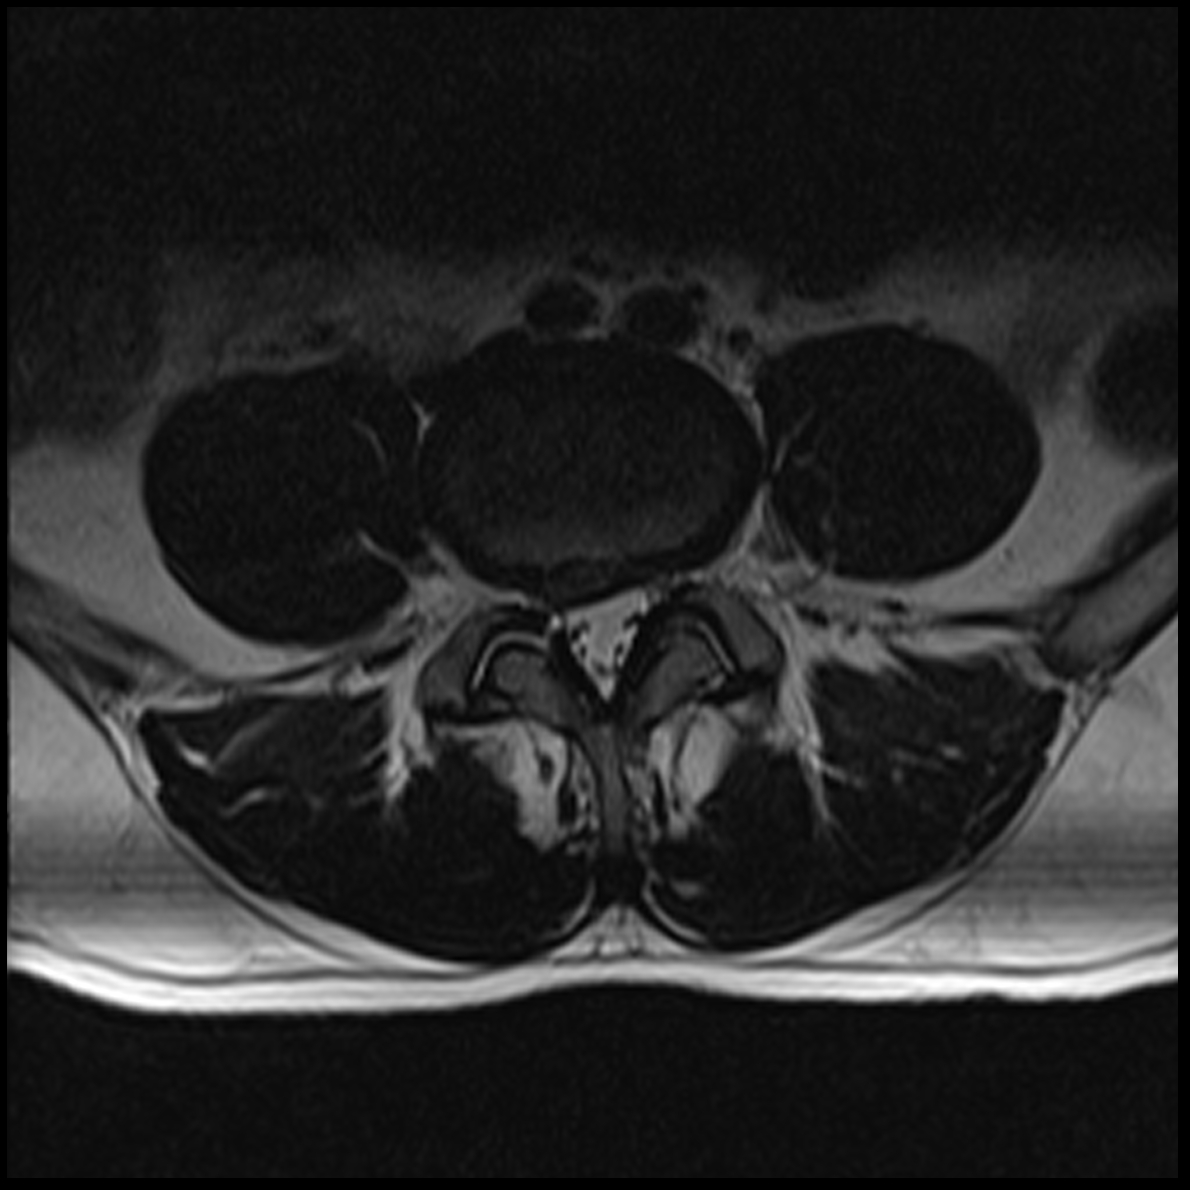

May 2019 MRI

IMPRESSION

- Near full-thickness tear of the anterior cruciate ligament femoral attachment with

associated edema in the intercondylar notch. This is best seen on axial and coronal

images. - Pivot shift bone contusions in a pattern typical of this injury.

- Medial meniscus: Complex tear of the posterior horn of the peripheral third

compromising superior and inferior articular surfaces, with the tear more horizontal

towards the posterior horn/body junction.